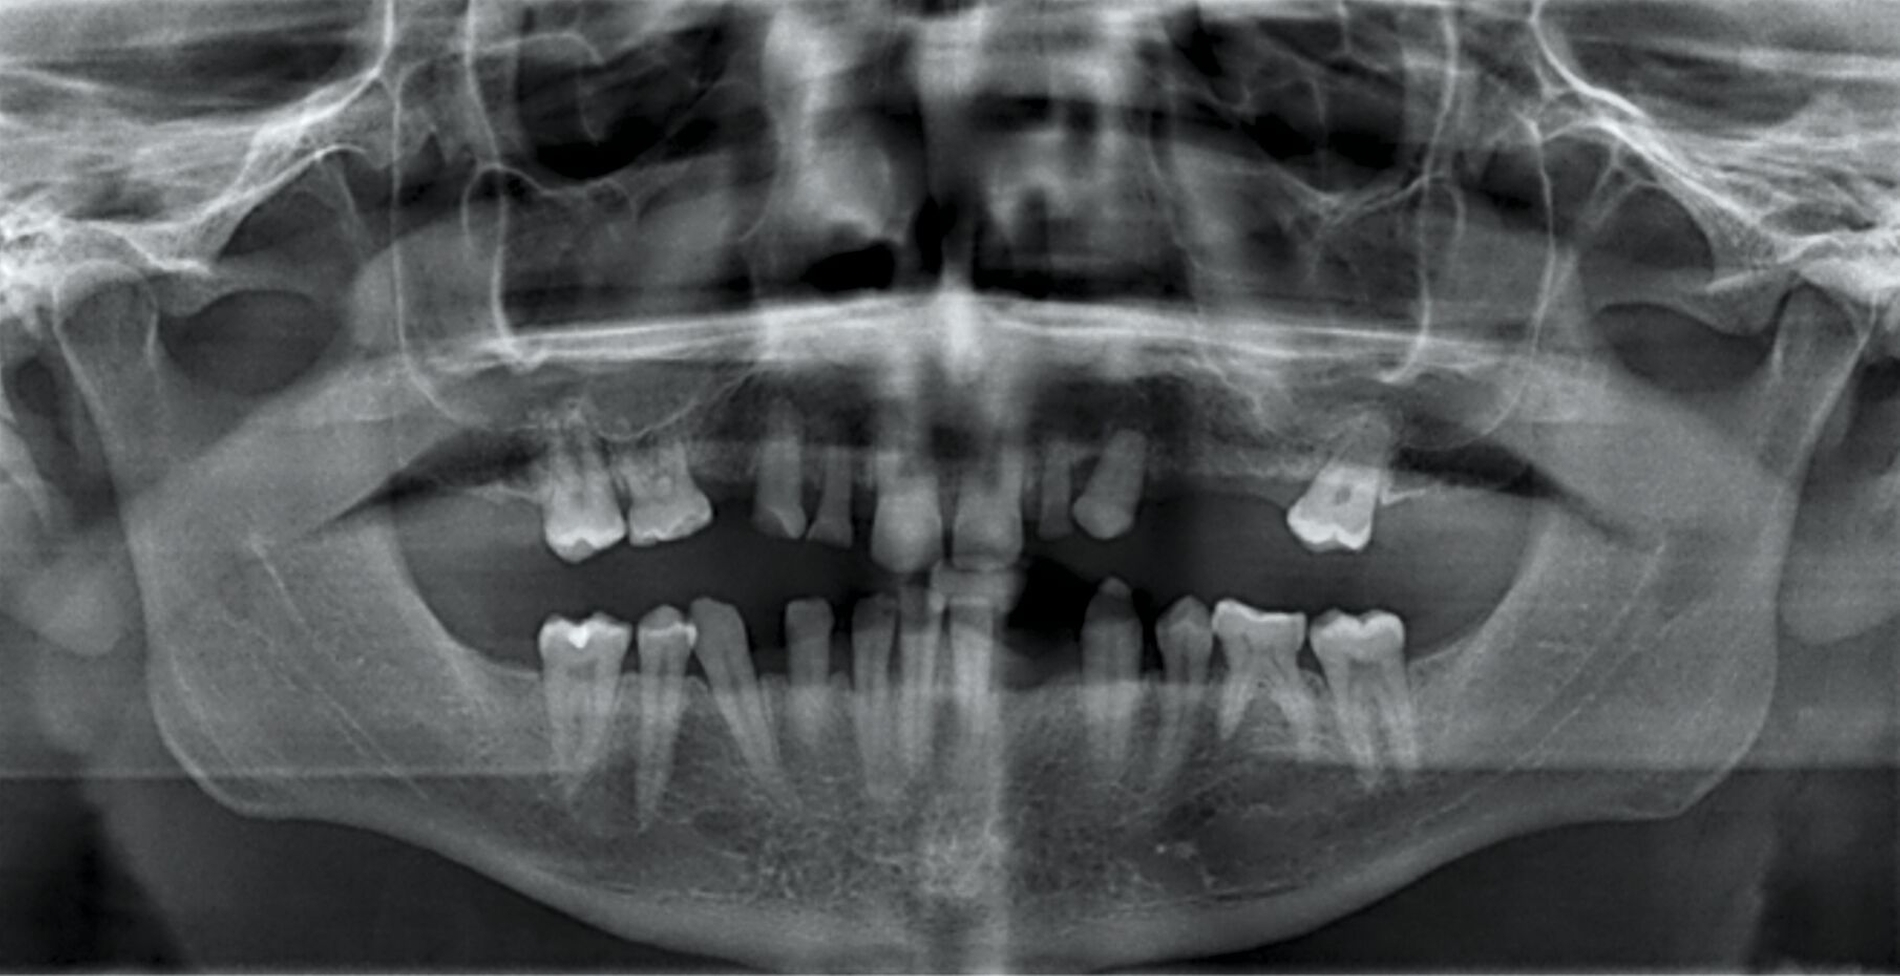

Zu Beginn der Behandlungsplanung wurden ein digitales OPG sowie Planungsmodelle erstellt (Abbildung 2). Interdisziplinär wurden mit dem Prothetiker, Chirurgen und Zahntechniker anhand der vorliegenden Modellanalysen und der klinischen Situation des Patienten verschiedene Therapieoptionen entwickelt und gemeinsam bewertet.